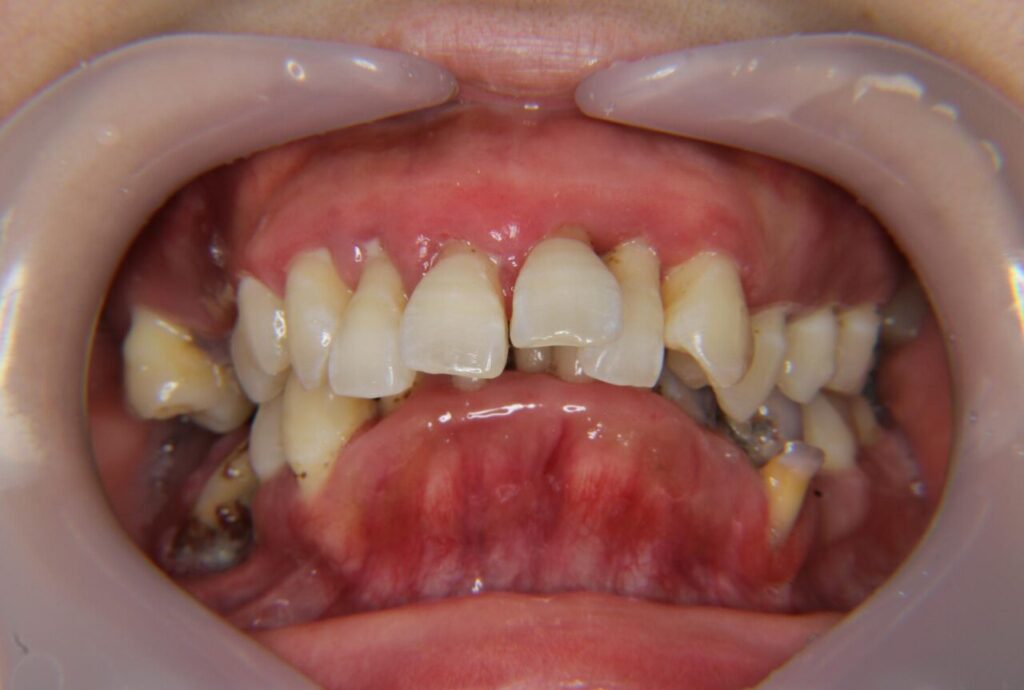

歯周外科手術と歯槽骨整形術で治療した症例

ほぼ全顎で外科手術を行い、歯茎だけでなく歯槽骨の整形手術も行いましたが、すべて保険診療で治療した症例です。